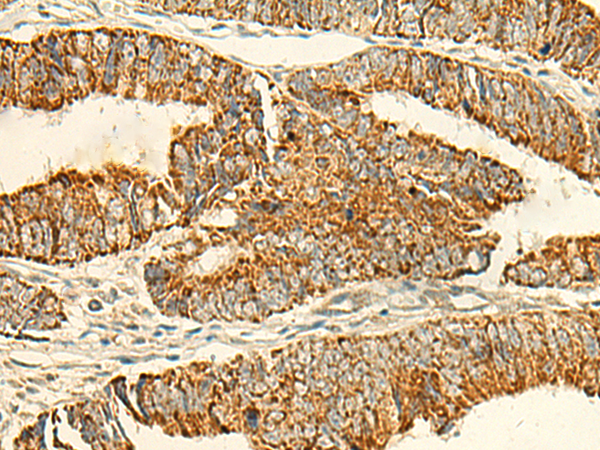

IHC positive control: |

Human tonsil and Human colorectal cancer |

IHC Recommend dilution: |

50-300 |